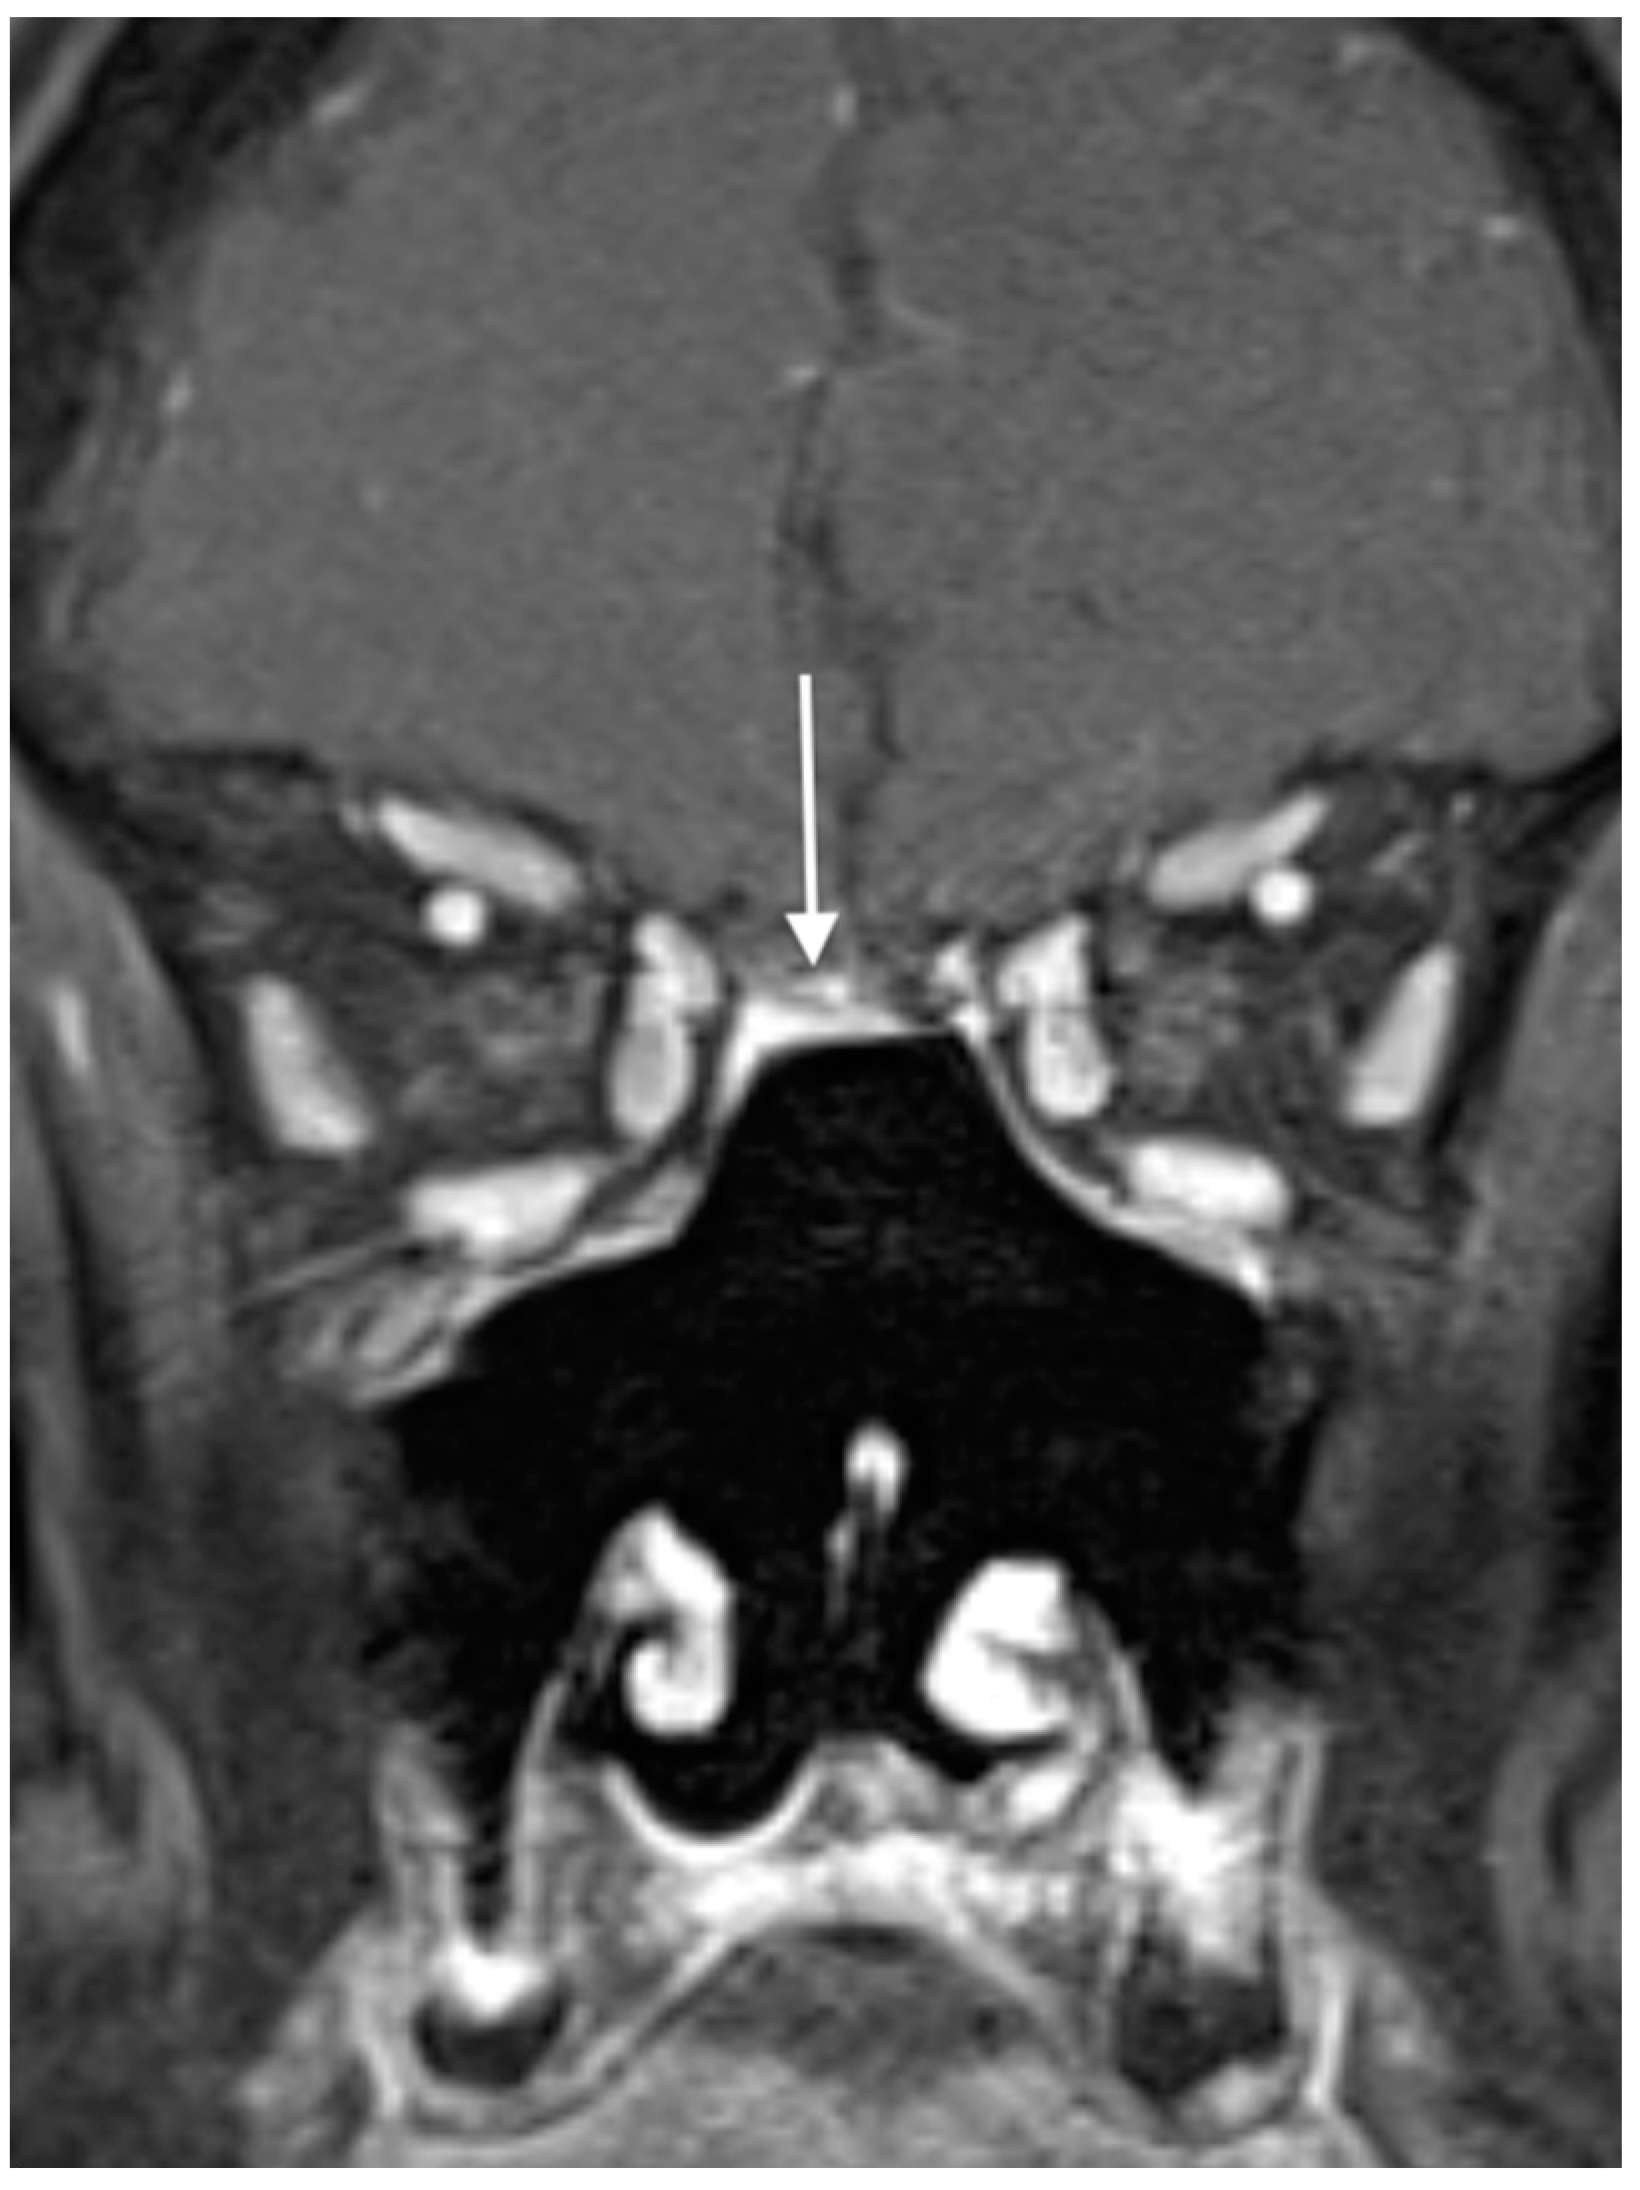

2. Patient- and Tumor-Specific Factors

- Geltzeiler, M.; Choby, G.W.; Ji, K.S.Y.; JessMace, C.; Almeida, J.P.; de Almeida, J.; Champagne, P.O.; Chan, E.; Ciporen, J.N.; Chaskes, M.B.; et al. Radiographic predictors of occult intracranial involvement in olfactory neuroblastoma patients. Int. Forum Allergy Rhinol. 2023, 13, 1876–1888. [Google Scholar] [CrossRef] [PubMed]

- Dublin, A.B.; Bobinski, M. Imaging Characteristics of Olfactory Neuroblastoma (Esthesioneuroblastoma). J. Neurol. Surg. B Skull Base 2016, 77, 1–5. [Google Scholar] [CrossRef] [PubMed]

| T1 | Tumor involving the nasal cavity and/or paranasal sinuses (excluding sphenoid), sparing the most superior ethmoidal cells |

| T2 | Tumor involving the nasal cavity and/or paranasal sinuses (including the sphenoid) with extension to or erosion of the cribriform plate |

| T3 | Tumor extending into the orbit or protruding into the anterior cranial fossa |

| T4 | Tumor involving the brain |